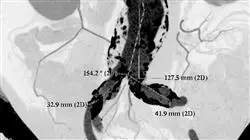

Die klinische Ultraschalls des Abdomens hat sich in den letzten zehn Jahren erheblich weiterentwickelt, nicht nur in Bezug auf die Technologie und die Bildauflösung, sondern auch in Bezug auf ihre vielfältigen und umfassenden klinischen Anwendungsmöglichkeiten. Von der Frühdiagnose von Lebererkrankungen bis hin zur dynamischen Beurteilung von entzündlichen Darmprozessen hat diese Technik bewiesen, dass sie wichtige Informationen zur Steuerung der Behandlung und zur Verbesserung der klinischen Ergebnisse liefern kann. In diesem Sinne müssen Kliniker ihr Wissen regelmäßig auf den neuesten Stand bringen, um den größtmöglichen Nutzen aus diesem Instrument zu ziehen und detaillierte Bilder zu erhalten, die die klinische Entscheidungsfindung erleichtern.

In diesem Rahmen führt TECH ein innovatives Programm im Bereich des klinischen Ultraschalls des Abdomens durch. Der von Spezialisten auf diesem Gebiet konzipierte Studiengang wird sich mit dem anatomischen Gedächtnis verschiedener Organe befassen, darunter Bauchspeicheldrüse, Nieren und Milz. Dies wird es Ärzten ermöglichen, anatomische Strukturen in medizinischen Bildern genau zu erkennen und zu beurteilen, so dass detaillierte Diagnosen gestellt werden können. Außerdem steht die ECO-FAST-Methode auf der Tagesordnung, mit der Experten lebensbedrohliche Zustände wie innere Blutungen diagnostizieren können. Ein weiterer Schwerpunkt des Programms sind die technischen Anforderungen an Ultraschallgeräte, einschließlich der Arten von Schallköpfen für die Abtastung des Abdomens und der Vorbereitung der Patienten.

Dieser Universitätskurs vermittelt ein ganzheitliches Verständnis der physikalischen Grundlagen des Ultraschalls und der Bildentstehung sowie der Anatomie des Abdomens. Zu diesem Zweck wird im Lehrplan das anatomische Gedächtnis vertieft, wobei der Schwerpunkt auf Organen wie der Bauchhöhle, der Leber und der Gallenblase liegt, um nur einige zu nennen. Die Studenten werden somit in der Lage sein, anatomische Strukturen in der medizinischen Bildgebung genau zu erkennen und zu beurteilen. In diesem Zusammenhang wird ECO-FAST-Methode untersucht, eine Technik, mit der Ärzte innere Blutungen aufgrund schwerer traumatischer Verletzungen erkennen können.